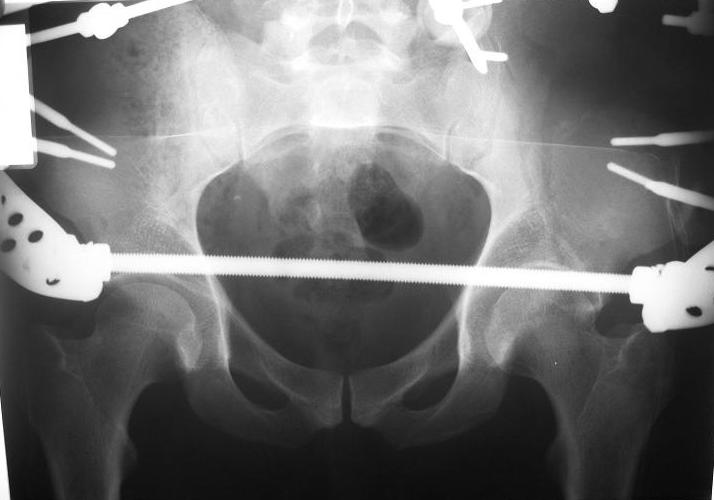

Поступил пациент после кататравмы (упал с высоты 4м). После обследования установлен Ds: Сочетанная травма. ЗТГК перелом 5-6 ребер справа. Ушиб левого леогкого. Оскольчатый перелом крыла подвздошной кости слева, со смещением. в экстренном порядке выполнена операция о/синтез таза стержневым аппаратом. Снимки прилагаются. Пациент со 2-го дня стал ходить без костылей. Из анамнеза жизни у пациента имеется гепатит В и С, с 1998г. употребляет наркотики (героин 1г в день нормальная доза). На контрольных снимках таза в аппарате смещение отломков сохраняется, да еще и стержни сломались. Подскажите ув.коллеги, как поступить в данной ситуации: оставить все как есть или добиваться репозиции в аппарате, или планировать на открытую репозицию. На сегодняшний день пациент стабилен, по анализам компенсирован. Принимает героин по другому справиться не может. С ув. Андрей

А сколько времени прошло после травмы? Аппарат лучше убрать: в таком виде он не выполняет никаких функций, а сломанные стержни скорее всего воспалятся и помешают доступу, если решите оперировать открыто. Целесообразно, как мне кажется сделать проекции Judet, чтоб определиться с линией перелома и возможным вовлечением вертлужной впадины. Вообще же лечение переломов крыла аппаратом - дело достаточно утомительное и часто неблагодарное - сложно управлять ротационным смещением и отведением/приведением фрагментов крыла, можно ухудшить стояние отломков.

Уважаемый Андрей, у пациента имеется перелом передней колонны,и после наложения аппарата положение отломков ухудшилось. возможно не из-за ваших действий а за счет тяги четырехглавой мышцы. Обе ости настойчиво будут тянуть крыло вниз.

C момента травмы прошло ровно 10 дней. Да Максим, вы как в воду глядели, у стержней появились признаки воспаления. Аппарат демонтирую.